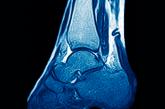

ArticleIs nonoperative treatment effective for acute Achilles tendon rupture?Author:Sabrina Silver, DO, CAQSMPublish date: June 15, 2022EVIDENCE-BASED ANSWER: YES. Nonoperative and open sur- gical interventions provide equal long-term functional outcomes of the affected Achille...Read More